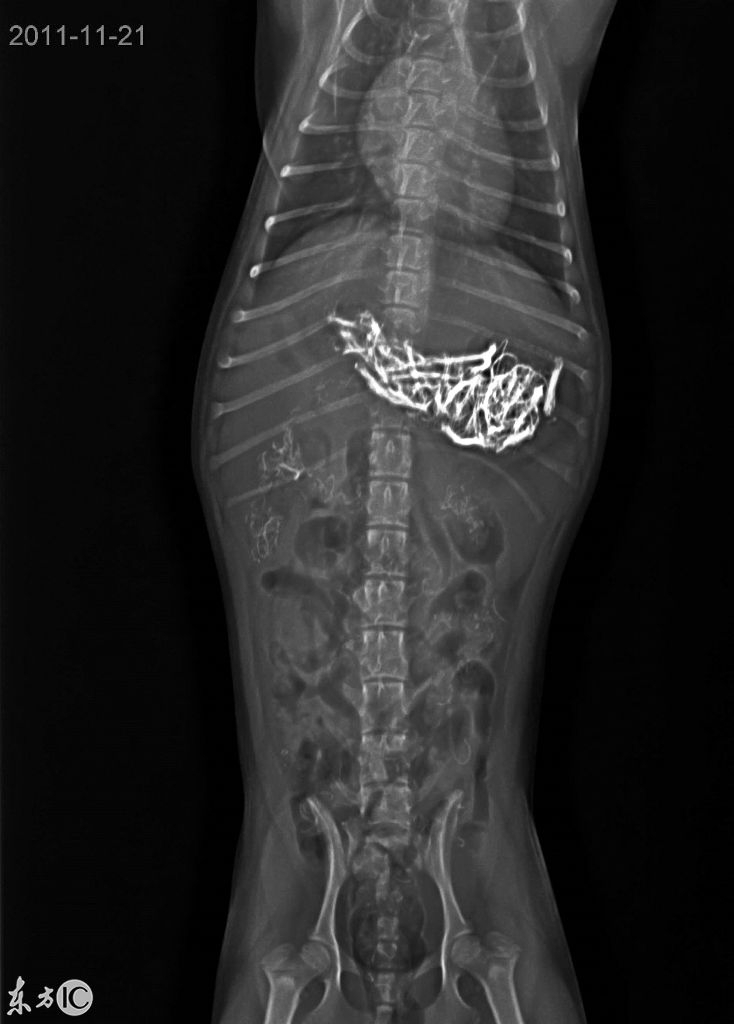

奇葩宠物们都爱吃些什么?这些X光照片告诉你

它们吃了什么?!兽医们收治了吞下各种奇葩物件的宠物,有些真是难以置信。这些的照片对宠物的主人来说可能会不忍直视,因为它们的肚子里的东西千奇百怪。这是一只小狗吞下了一个手机充电器。(图片来自东方IC)一只爱尔兰软毛犬吃下了主人的耳机。呃~~想想从嗓子到肠子都难受。(图片来自东方IC)一只2个月大的捕鼠梗犬吃下了它主人的内衣扣,话说不觉得卡嗓子吗?可能是误吞吧。但是下面的这些...阅读全文>&g... 阅 读 全 部 >